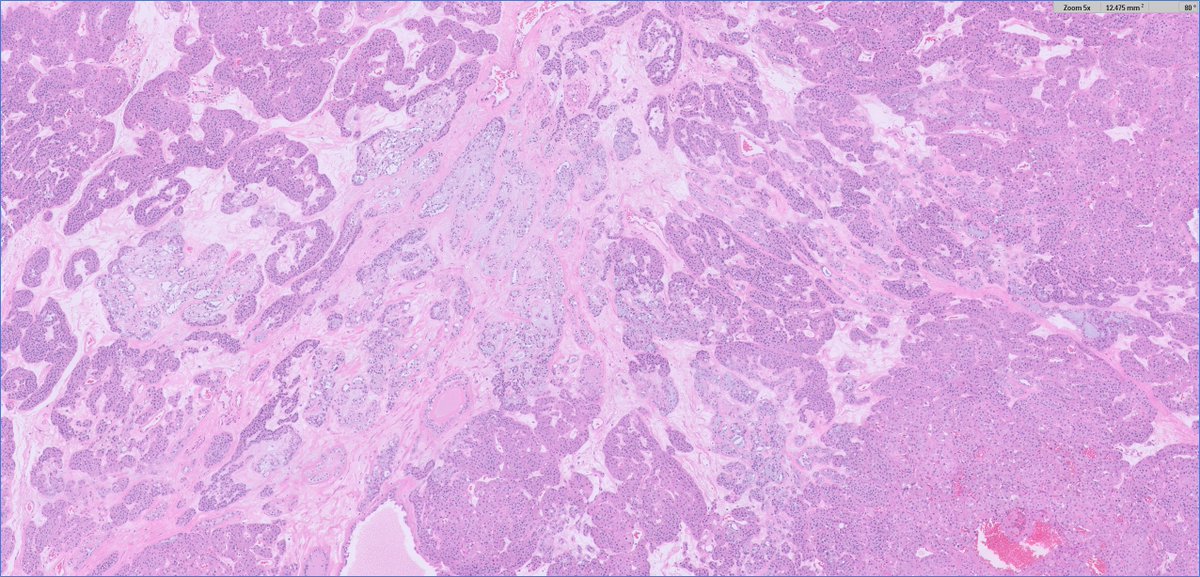

Placental Site Trophoblastic Tumor • RARE malignant trophoblastic neoplasm from intermediate trophoblasts • Mean Age: 31 • 2/3 cases follow full term pregnancy (median latency 12-18 months) • 🩺: Vaginal 🩸, uterine enlargement • ~25-30% may develop recurrent dz